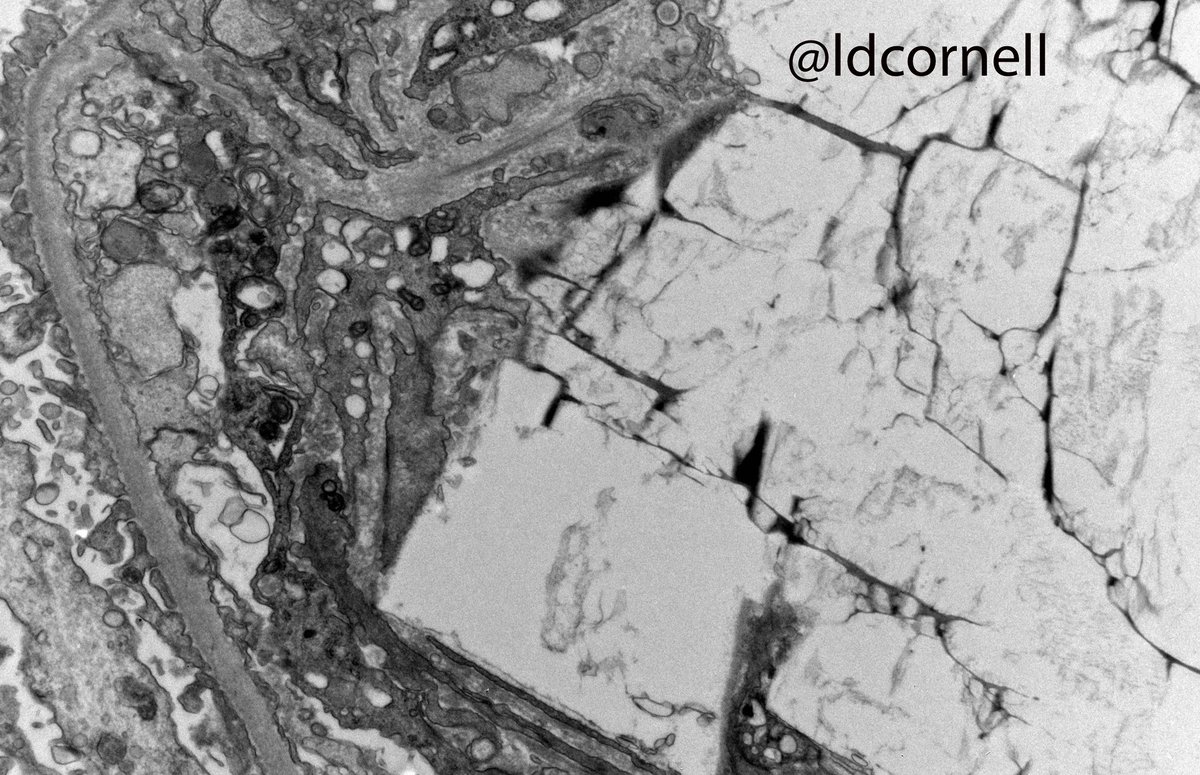

Kidney transplant biopsy from an adult man, 10 months post-transplant. ESRD was due to IgAN. This biopsy was for increased creatinine and proteinuria. Quiz: what are these crystals? (I am intentionally withholding some clinical info!) #renalpath Renal Pathology Society